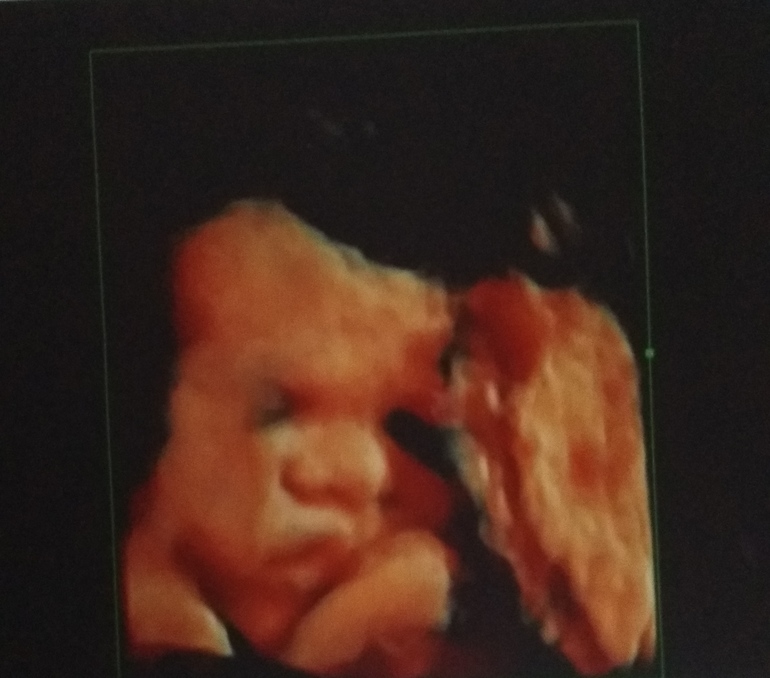

Наш щекастый малыш😍 34+2, ~2700гр. Поделитесь про вес)

Какой сладеныш🤗🤗🤗ттт

Пупсик) Моему примерно на этом же сроке ставили 2800))

Какой пухленький малыш 🥰 моя бусинка в 32.4 весила 1900.